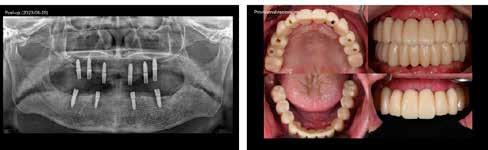

Dr. Gáspár Lajos

RÖVID ÉS KESKENY IMPLANTÁTUMOK AKTUÁLIS KONSZENZUS KÉRDÉSEI

A XXI. század fogászatának egyik legdinamikusabban fejlődő ágazata a fogászati implantológia, napról napra újabb és újabb kérdéseket, kihívásokat jelent, melyekre újabb és újabb, ma már konszenzuson alapuló válaszok születnek. Ezek nagyban segítik a gyakorló orvosokat a helyes és biztonságos megoldások kiválasztásában, a rizikó csökkentésében, továbbá a kiszámítható, minél kevésbé invazív eljárások alkalmazásában. Ez az iránymutatás és ezek megerősítése meghatározó jelentőségű a szakma fejlődése és tudományos megalapozottsága szempontjából.

1. ábra: Dr. Jung 10 éves kontrollal rendelkező 4.7-es helyén levő Dentium short implantációja. Preoperativ CT, ínyformázó 4 hónappal a műtét után, valamint 4 hónap múlva 4.7-es szólókorona.

Az USA-ban működő Global Market Insights Inc. az egész világra kiterjedő felmérései szerint (https://www.gminsights.com/ industry-analysis/dental-implants-market) évi 6,5%-os forgalomnövekedés tapasztalható a fogászati implantológiában a világpiacon, és 15 év alatt a forgalom a duplájára nőtt. Az implantológia világpiaci, fontosabb tényezőinek vizsgálata során elemezték a gyökér formájú vagy a párhuzamos, a titán- vagy a cirkonimplantátumokat. A végfelhasználás kórházakban, magánklinikákon vagy egyéb helyen történik. Mindezt minden földrészen elemzik. Megállapították, hogy 2018–2022 között a titánimplantátumok forgalma 24%-kal, a cirkonok 27%-kal növekedett. 80% titán és 20% cirkon a jelenlegi felhasználás aránya. A gyökér formájúak forgalma 21%-kal, a párhuzamos falúaké 29%-kal növekedett. Jelenleg 80%-ban gyökér formájút, 20%-ban parallelt használnak. Az implantátumok végfelhasználása elsősorban magánklinikákon történik. A Biomaterial Research 2022. évi 26. számában „Worldwide patent landscape of dental implant technology” című cikkükben Woo Jin Kim és mtsai. arról számolnak be szakfolyóiratok széles körű analízise alapján, hogy 2000–2020 közötti 20 év alatt a levédett

2. ábra: Dr. Park esete. 4.6-os fogon levő jelentős csontfelritkulás röntgenképe, extractio és iGBR alkalmazása Osteon Xenoval. 4 hónap múlva Dentium short implantátum, majd 4 hónap múlva korona készítése.

A páciensek jelentős része nem elegendő csonttal rendelkezik, ugyanakkor mindenáron fix pótlást szeretne. Sokan elzárkóznak a hagyományos megoldást jelentő csontpótlástól, és napról napra felmerül a kérdés: milyen feltételek között lehetséges bizonyos szempontból a csontpótlás alternatívájaként jelentkező rövid és keskeny implantátumokkal megoldani a csonthiányos eseteket?

Ezt az igen aktuális témakört tűzte napirendre 2023. október 29-én Dél-Koreában, Szöulban a COEX-ben „Short and Narrow Consensus” címmel a Dentium cég szervezésében megrendezett nemzetközi implantológiai szimpózium, melyen az egész világról 1500 fogorvos vett részt.

A konferencián elsőként a Szöuli Egyetem Professzora, Kim Sung Tae „Consensus Guidline for management of Deficient Alveolar Ridge” címmel tartott előadást. Felvetette számos eset bemutatásán keresztül a grafttal vagy graft nélküli megoldások dilemmáját, pró és kontra érveket, és hogy miként lehetséges az eredmények optimalizálása, továbbá a rizikó minimálisra csökkentése.

Az esetek jelentős részében, ahol a csonthiány mértéke egy határt már meghalad, megállapította, hogy a rövid és keskeny implantátumok kiváló alkalmazhatósága ellenére csak graftok alkalmazása teszi lehetővé az implantátumok biztonságos behelyezését.

Dr. Jerry Lin, a Harvard parodontológusa a rövid implantátumok rizikókérdéseivel foglalkozott. Kiemelte, hogy az implantológia létezése óta folyamatos törekvés a komplikációk csökkentése, a minimál invazivitás, a betegek diszkomfortjának a csökkentése. Ebben a short implantátumok új fontos szerepre tettek szert. A múltban a 10 mm-es és annál hosszabb implantátumok alkalmazása terjedt el elsősorban. A „Minél hosszabb, annál jobb” elvet követték. Majd megjelentek a 8 mm-es és az ennél rövidebb, short implantátumok, később a 6 mm-nél is rövidebb, ultrashort műgyökerek. Megfelelő átmérő esetén – lehetőleg 5 mm-es vagy annál nagyobb átmérővel – a rövid implantátumok alkalmazása ma már elfogadottá vált és szakmailag bevált eljárásnak tekinthető. Új szemlélet elterjedésének és elfogadásának lehetünk a tanúi.

Prof. Jung Ui Won szöuli parodontológus a rövid implantátumok rizikómenedzselésével foglalkozott előadásában. Eseteket mutatott be 10 éves követéssel, ahol rendkívül alacsony csontkínálat mellett tudott sikeresen short megoldást találni.

Dr. Park Jung Chul, a szöuli Katolikus Egyetem előadója a páciens és orvos-barát megoldásként alkalmazott, nyitott gyógyulású iGBR technikával foglalkozott. Egyik esetében a jobb alsó 6-os fogon periapicalis léziót mutatott be, majd extractio, iGBR alkalmazása, és 4 hónappal később implantáció, továbbá korona készítése történt.

Park doktor előadásának második részében a súlyos, csonthiányos állapotok Dentium Osteon Xeno csontpótló alkalmazásával szerzett tapasztalatairól számolt be. Megállapította, annak ellenére, hogy rendkívül kedvezőek a tapasztalatok a rövid és keskeny implantátumokkal, egyre szélesebb körben alkalmazhatóak, nem lehetséges minden eset megoldása ezekkel, mert nem csodaszerről van szó. Nem lehetséges sok esetben

3. ábra: Dr. Han esete. 2.4-2.5-2.6 lokalizációban keskeny gerinc. Csontpótlás Osteon Xeno- val, majd 4 hónap múlva 3 db Dentium short implantátum behelyezése. 4 hónappal később protetikai munka.

4. ábra: Dr. Chung esete. Short implantátumok 10 éves kontrollja a 4.7 és 1.6-1.7 lokalizációban.

5. ábra: Dr. Chun esete. Dentium Narrow implantátumok és azok protetikai ellátása 4 hónappal a beültetést követően.

6. ábra: Dr. Lim esete. Dentium Narrow implantátumok a felső állcsonton, guide tervezés, ideiglenes hídpótlás azonnali terheléssel, majd 4 hónappal később végleges protetikai ellátás.

csontpótlás nélkül a jó megoldás. A konszenzusos elveket be kell tartani.

Dr. Han Seung Min szöuli parodontológus szintén csonthiányos esetek Osteon Xeno-val történő sikeres rekonstrukciójáról és short implantátumokkal történő megoldásáról számolt be.

A Dentium cég elnöke, dr. Chung Sung Min a „Minimalizmus rövid és keskeny implantátumokkal” címmel tartott előadást. Kiemelte, hogy mind az alsó, mind a felső állcsonton elsősorban a moláris régióban találkozunk alacsony gerinccel, ahol a short implantátumok ma már igazoltan jó, biztos és bevált megoldást jelentenek. Ezzel már több mint 10 éves tapasztalatok állnak rendelkezésre, és konszenzus alakult ki az alkalmazásuk feltételeiről, melyben az ITI nemzetközi ajánlásait tartja a Dentium is követendőnek.

Dr. Chun hangsúlyozta a felső és alsó frontterület gyakori keskeny gerincét, ahol kedvezően alkalmazhatóak a keskeny implantátumok.

Dr. Chun kiemelte, hogy a rövid és keskeny implantátumok alkalmazása ma már forradalmasította az implantológiát, és újragondolásra késztette a klasszikus definíciókat. Fontos minden esetben a könnyebb, egyszerűbb, biztonságosabb, költséghatékony megoldások keresése. A Dentium implantátumok

7. ábra: Dr. Byun esete. Keskeny állcsontgerinc a jobb alsó és mindkét oldali felső laterális régióban. Implantáció Dentium Narrow implantátumokkal, majd 4 hónap múlva protetikai ellátás.

8. ábra: Dr. Chang esete. 2.4-es fog helyén keskeny gerinc. Csontpótlással együtt Dentium Narrow implantátum behelyezése. 4 hónap múlva korona készítése.

fejlesztése az ITI irányelvek figyelembevételével történik, és mind a rövid, mind a keskeny implantátumok területén lehetőséget nyújtanak ezek biztonságos alkalmazására.

Dr. Lim Sang Chui, a Szöuli Egyetem parodontológusa előadásában a digitálisan, guide segítségével keskeny gerincbe történő implantáció módszerét mutatta be. Elmondta, hogy világszerte elfogadott a minimálisan invazív módszerek alkalmazása, és különösen a keskeny állcsontgerinc esetén nagy jelentősége van a guide módszernek.

Dr. Ha-Kien Oon a szájsebész társaság elnöke, a malajziai egyetemről „Tényleg számít a méret?” című előadását a Branemark által megfogalmazott elvek elemzésével kezdte. A fejlődés új elemeket hozott, így az azonnali implantációt, a bicorticalis elhelyezést, a protetika által vezérelt behelyezést. Ezek egyre minimálisabb invazivitáshoz, egyre nagyobb kiszámíthatósághoz vezettek, és egyre többet értünk meg az emberi szervezet és az implantátumok kapcsolatából. Felmerül a kérdés, hogy milyen tényezők figyelembevételével döntünk az implantátumok méretének meghatározásakor? A körültekintő diagnosztika és a konszenzuson alapuló irányelvek segítségével a méretválasztásban ma már sok segítséget kapnak az implantológusok. Javasolja,

hogy az ITI konszenzus ajánlásait vegyék figyelembe.

Prof. Byun Soo Hvan, a Szöuli Egyetem szájsebésze „A minimal GBR technika alkalmazása keskeny implantátumok esetén” témakörben tartott előadást.